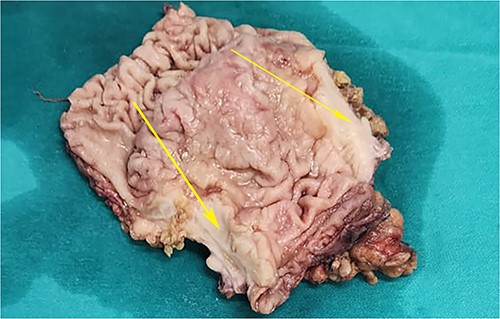

On laparotomy, the gastric antrum was infiltrated with a tumour with no serosal extension (Fig. 4), no ascites, and bilateral ovarian cysts (right: 12 × 10 × 6 cm, left: 9 × 5 × 4 cm) (Fig. 5). An R0 resection that included D2 gastrectomy and pan-hysterectomy was performed. The patient made an uneventful recovery and was discharged on the 15th postoperative day. The final diagnosis after histopathological examination was diffuse infiltrating gastric carcinoma signet cell-type (Figs 6 and 7), LP, KT deposits in both the ovaries (Fig. 8), with regional lymph node involvement (Fig. 9) in two nodes among the 15 nodes that were dissected. The staging was T4a, N1, and M1. The patient decided against adjuvant treatment. She was disease-free on clinical and radiological examinations at 12 months.

Postoperative specimen of the stomach showing intramural tumour at the pyloric antrum (arrow).